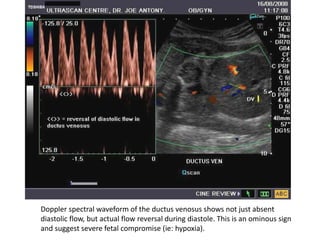

Doppler spectral waveform of the ductus venosus shows not just absent

diastolic flow, but actual flow reversal during diastole. This is an ominous sign

and suggest severe fetal compromise (ie: hypoxia).